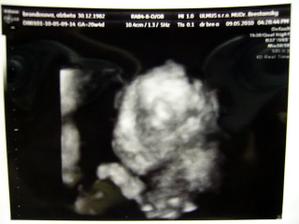

♥ 09.05.2010 sme boli na 3D ultrazvuku. Malý krásne tancoval a stále si cucal pršteky. Nebolo ho veľmi dobre vidieť kvôli placente, ale dr ho pomeral a všetko je ok. Naše milované chlapčiatko je úplne zdravé. Veľmi sa tešíme